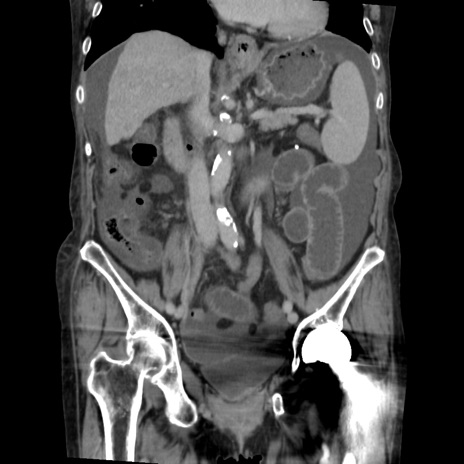

症例31(冠状断像)

【症例】80歳代 女性

【主訴】腹部膨満感

【現病歴】他院にて肝硬変にてフォロー中。1週間前から便秘、腹部膨満感、臍部腫瘤あり受診となる。

【既往歴】肝硬変

【身体所見】腹部膨隆あり、皮膚変化なし、疼痛なし。

【データ】WBC 4600、CRP 0.25